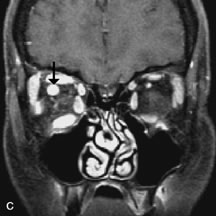

Lacrimal Gland Tumors

Lacrimal gland lesions present special problems in diagnosis and management. Pleomorphic adenoma (benign mixed tumor) should not be biopsied, but rather excised in toto. On the other hand, for lymphoma and inflammatory infiltrates, incisional biopsy is more appropriate than complete excision of the lacrimal gland. Thus, preoperative clinical and radiologic evaluation are especially crucial in planning appropriate surgical management.

Pleomorphic adenomas demonstrate long T1 and T2 signal characteristics. They may show heterogeneity on T2-weighted images74 and moderate to marked enhancement with contrast.75 Signal characteristics of adenoid cystic carcinoma include hypointensity to fat on T1-weighted images, hyperintensity to fat with increased T2 weighting, and isointensity to fat on proton density-weighted studies (Fig. 23).31,75 Secondary bony alterations of the lacrimal fossa associated with lacrimal gland tumors, such as remodeling (benign mixed tumor) or destruction (adenoid cystic carcinoma), are seen indirectly on MR images; however, bone windows on CT scans provide better delineation of these changes. In contrast to the round or globular appearance of benign or malignant epithelial tumors of the lacrimal gland, lymphoproliferative tumors usually appear to be molding or draping onto the globe and the surrounding bony orbit.

Fig. 23. A. T2-weighted and (B and C) postcontrast fat-suppressed T1-weighted MR scans demonstrate an infiltrative lacrimal region mass than invades the lateral rectus muscle (arrows). This highly cellular lesion is seen to have a very hypointense appearance on the T2-weighted scan.